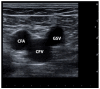

Keywords: CEAP; chronic venous disease; great saphenous vein; varicose veins.